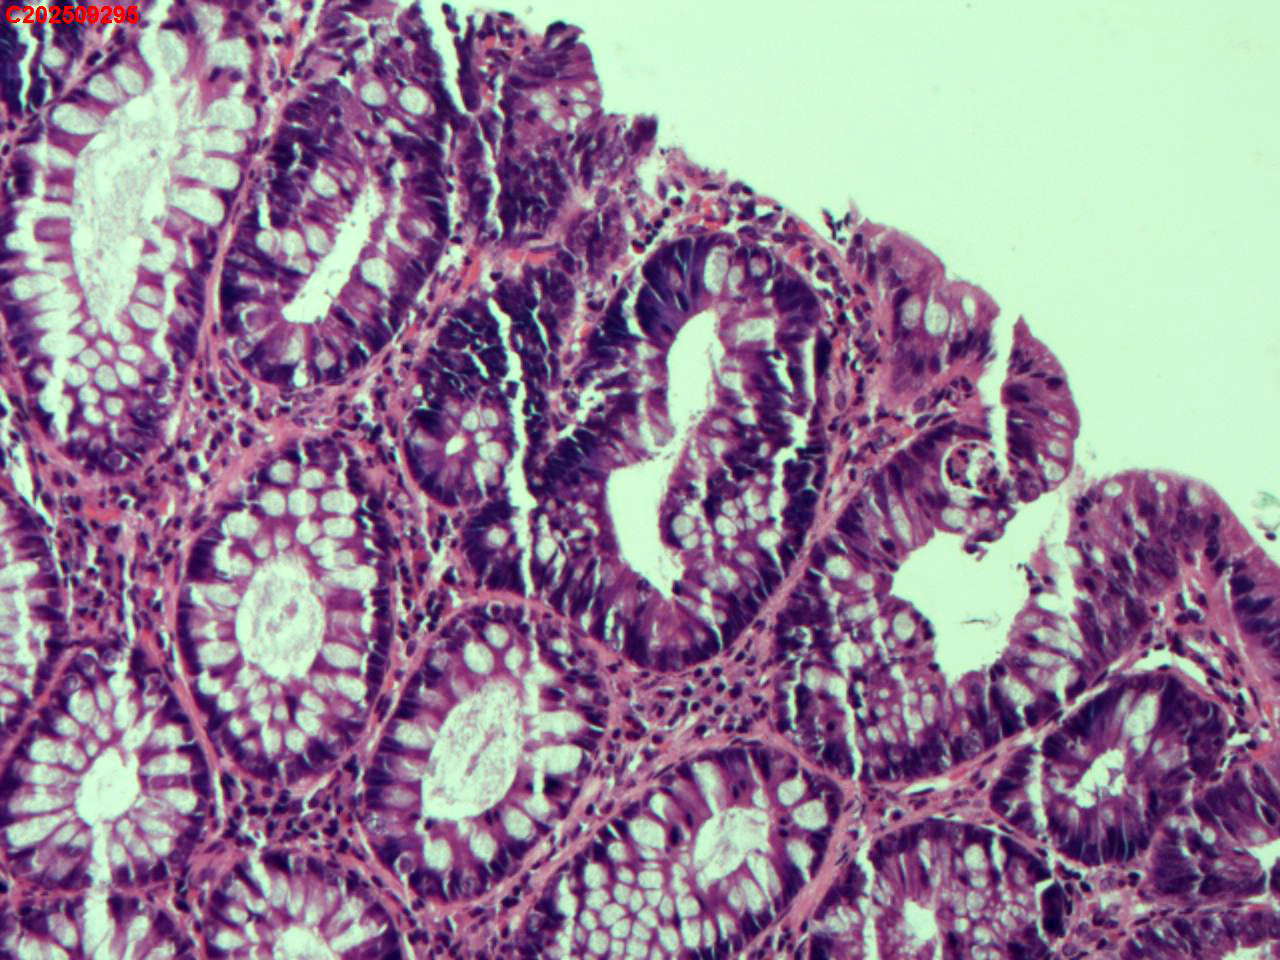

降结肠粘膜

性别

男

年龄

48岁

临床诊断

结肠息肉

一般病史

体检

标本名称

大体所见

降结肠:可见一枚直径约3mm息肉。

低级别管状腺瘤

管状腺瘤。